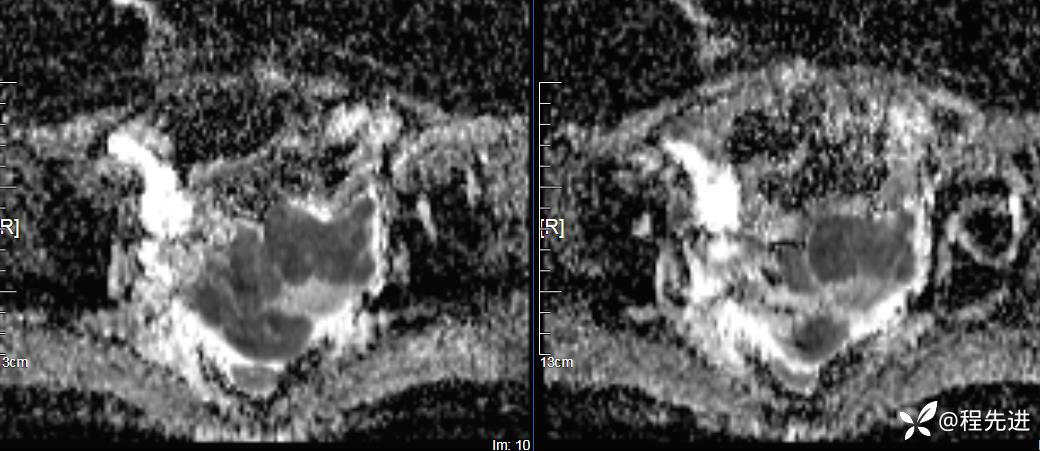

DWI、ADC: